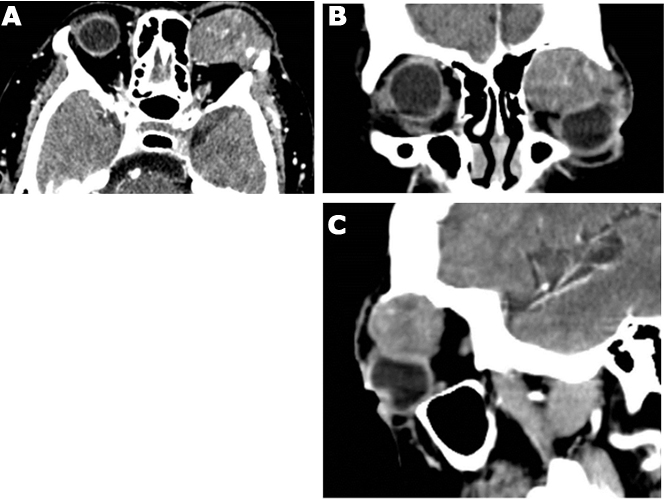

Examination of left eye showed, corrected visual acuity of counting fingers 3 feet, relative afferent pupillary defect, superior choroidal folds, and optic disc swelling. Examination of right eye was normal. Computerized tomography demonstrated an extraconal, wellcircumscribed mass lesion occupying superomedial part of the left orbit 2.3×2.3×3.7 cm in greatest dimensions with some areas of calcification and mild heterogeneous contrast enhancement. There was bony excavation of roof and medial wall of left orbit and indentation of superomedial globe (Figure 2A–C).

Figure 2: (A) Axial, (B) Coronal, and (C) Sagittal sections of CT orbit demonstrate a large, well-circumscribed, extraconal mass in superomedial orbit.